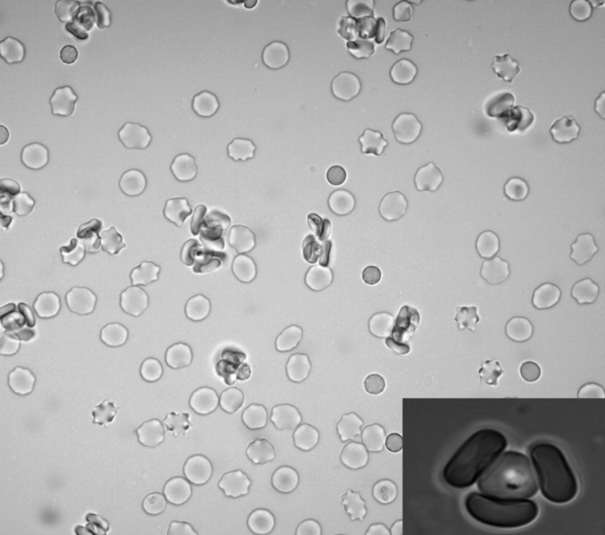

(A) P. knowlesi merozoite invading RBC. (B) P. falciparum trophozoite with hemozoin. (C-D) Knobs and membrane deformation by P. falciparum. (E) Cytoadherence. (F) Rosetting.